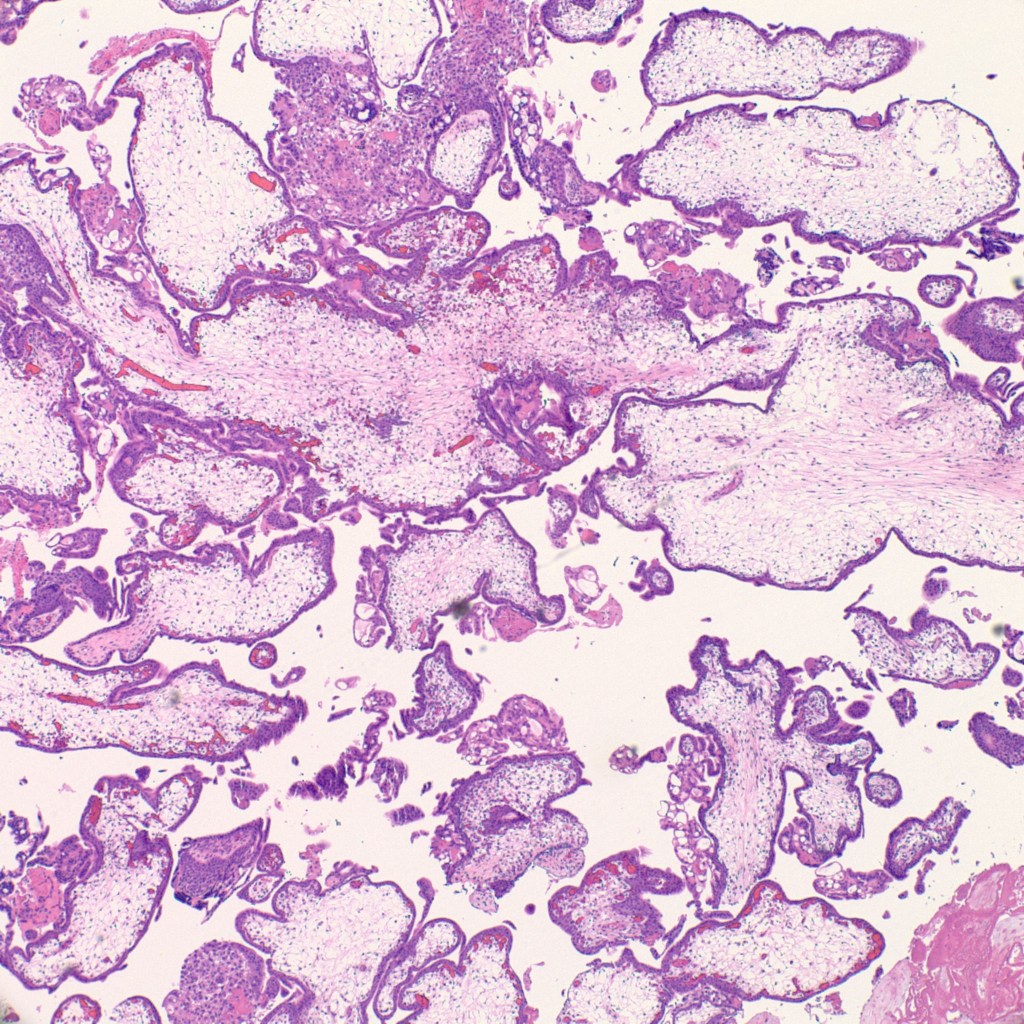

- Grossly large amount of tissue (5 cm and more) with sometimes large ballooned villi (>1 cm).

- Presence of cisterns, circumferential or almost circumferential trophoblastic proliferation and trophoblastic inclusions (figure 3-4).

- Blue myxoid stroma with karyorrhexis (figure 5).

- Atypical and exaggerated implantation site with large trophoblasts, at least three times larger than decidual cells (figure 6).

- 99.9% of the time there is no fetus and no nucleated red blood cells in the villi.